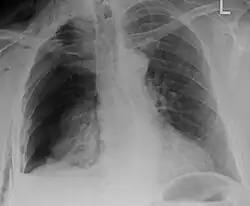

| An X ray showing multiple old fractured ribs of the person's left side as marked by the oval | |